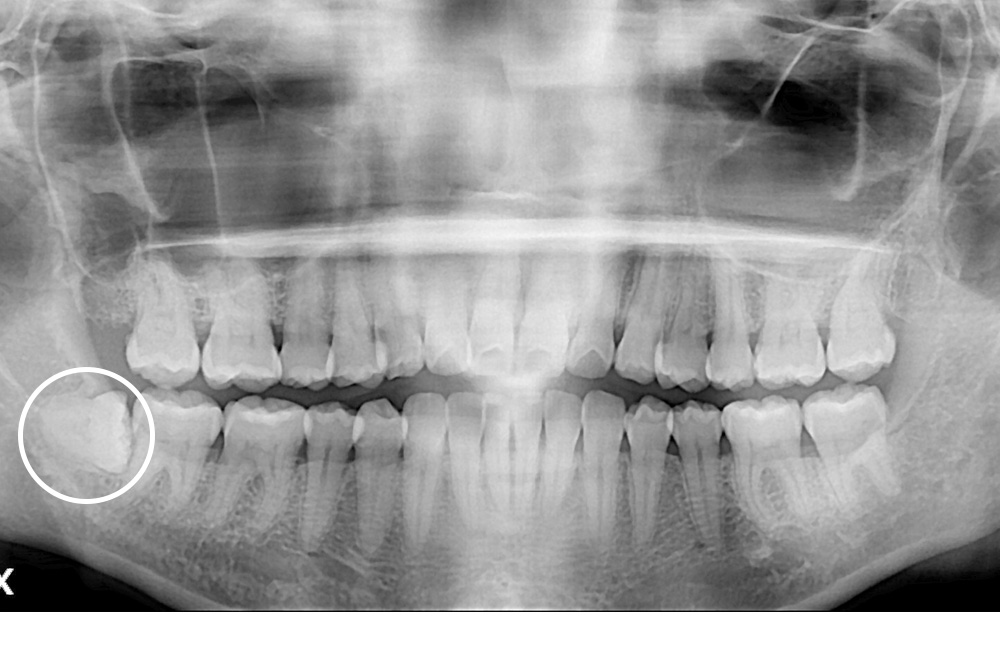

[사랑니] 매복 사랑니 발치

치료후 : 2021-07-09

세종치과는 구강악안면외과학 박사이신 원장님이 발치하는 치과입니다.